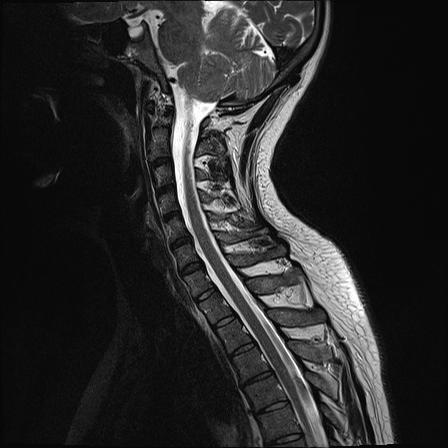

Meist tritt ein Bandscheibenvorfall auch in der Halswirbelsäule entweder streng rechtsseitig oder streng linksseitig auf Abbildung A und B. MRT-Aufnahme eines lumbalen Bandscheibenvorfalls Segment L5S1 im Längsschnitt der Wirbelsäule gelber Kreis. Wichtige Mikronährstoffe um Ihr 1.

Hier herrscht also nur ein Verschleiß der ebenfalls Schmerzen verursachen kann aber nicht muss. MRT Magnetresonanztomographie HWS HalswirbelsäuleBilder die nur Ärzte deuten könnenals Laie muss man da vertrauen habenFanshop. Leiden PatientInnen unter einer Lähmung an den Armen undoder Beinen treten Zeichen einer Rückenmarksbeteiligung auf Gangstörungen.

Lesen Sie hier welche Kontrastmittel verwendet werden und welche Risiken das Kontrastmittel-MRT birgt MRT HWS - Auswertung und Bilder. Anschließend ist links ein MRT-Schnittbild einer Halswirbelsäule mit Kontrastmittel zu sehen welche einen Bandscheibenvorfall im HWS. Zur Abklärung wurde eine Kernspintomographie der Lendenwirbelsäule durchgeführt.

Herz Herz-Kreislauf-System zu stärken. Ersichtlich die Fehlstellung der HWS und die Bandscheibenvowölbungen.

Jetzt meine neuen Ratgeber bestellen. Auf den MRT- CT-Schnittbildern werden die Größe und der genaue Ort des Vorfalls sichtbar. Ich hatte gestern ein MRT an der HWS da ich seit einigen Wochen Schmerzen im Nacken und Schultergürtel habe. Bei einem Bandscheibenvorfall in der Höhe C6C7 kommt es zu einem Druck auf die Nervenwurzel C 7 da diese zwischen dem Wirbelkörper C6 und dem Wirbelkörper C 7 aus dem Nervenloch Neuroforamen austritt. MRT-Bild und Beschwerdebild müssen. Röntgenbilder auf der Patienten-CD ansehenDer Bandsch. In dem Segment darüber Segment L4L5 sieht man eine deutliche Bandscheibenprotrusion die ebenfalls den Wirbelkanal einengt. In MRT-Sicht Bilder von einer Myelographie bei einer Prothese Nachfolgend ein paar Bilder von intakten Wirbelsäulen und Bandscheiben zum Vergleich. KernspintomographieKernspinmyelographie MRT Magnetresonanztomographie Durch eine fachgerecht durchgeführte MRT-Untersuchung erhält man die meisten Informationen über die Lokalisation Art und Ausdehnung eines Bandscheibenvorfalls.

In MRT-Sicht Bilder von einer Myelographie bei einer Prothese Nachfolgend ein paar Bilder von intakten Wirbelsäulen und Bandscheiben zum Vergleich. Ersichtlich die Fehlstellung der HWS und die Bandscheibenvowölbungen. MRT Magnetresonanztomographie HWS HalswirbelsäuleBilder die nur Ärzte deuten könnenals Laie muss man da vertrauen habenFanshop. Meist tritt ein Bandscheibenvorfall auch in der Halswirbelsäule entweder streng rechtsseitig oder streng linksseitig auf Abbildung A und B. Herz Herz-Kreislauf-System zu stärken. Bandscheibenvorfall der bis an. Zusätzlich Gefühlsstörungen und Kribbeln bis zu den Fingern.